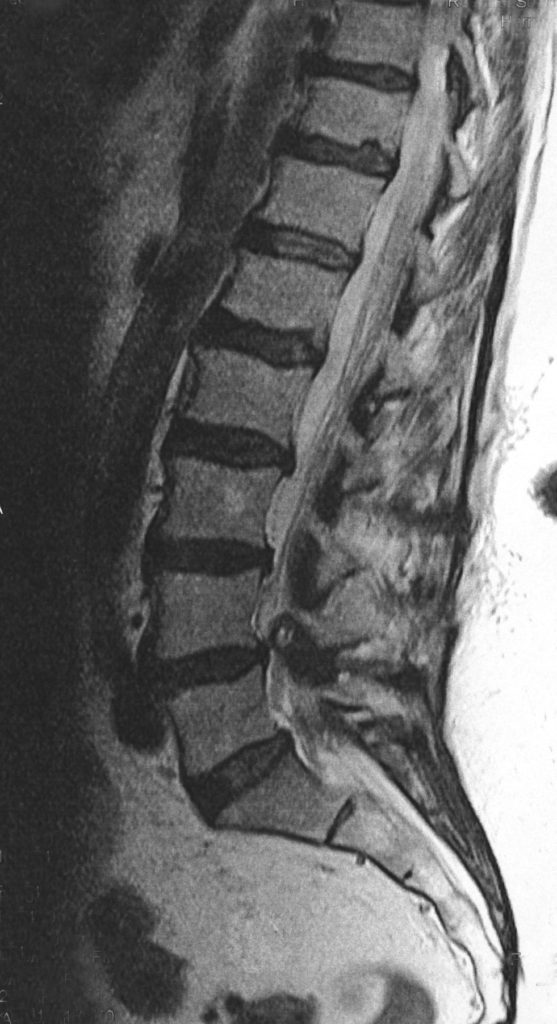

In den meisten Fällen entsteht eine Spinalkanalstenose durch altersbedingte Veränderungen der Wirbelsäule. Mit den Jahren nutzen sich die Bandscheiben ab, es bilden sich kleine Vorwölbungen, und knöcherne Umbauten an Wirbelkörpern oder Wirbelgelenken engen den Wirbelkanal zunehmend ein. So verringert sich der Raum für die Nerven zunehmend, und der Wirbelkanal, in dem das Rückenmark vom Gehirn bis in den oberen Lendenbereich verläuft, verengt sich. Meist sind Patienten betroffen, die das 60. Lebensjahr bereits überschritten haben.

Die Beschwerden hängen stark davon ab, wo die Verengung auftritt:

- Lendenwirbelsäule (LWS): Häufig kommt es zu Schmerzen im unteren Rücken, die beim Gehen oder Stehen in Gesäß und Beine (ein- oder beidseitig) ausstrahlen. Betroffene berichten oft, dass die Beine schnell ermüden und die Gehstrecke eingeschränkt ist. Typisch ist, dass sich die Beschwerden bessern, wenn man sich hinsetzt oder nach vorn beugt. Deshalb wird die Erkrankung manchmal auch als „Schaufensterkrankheit“ bezeichnet.